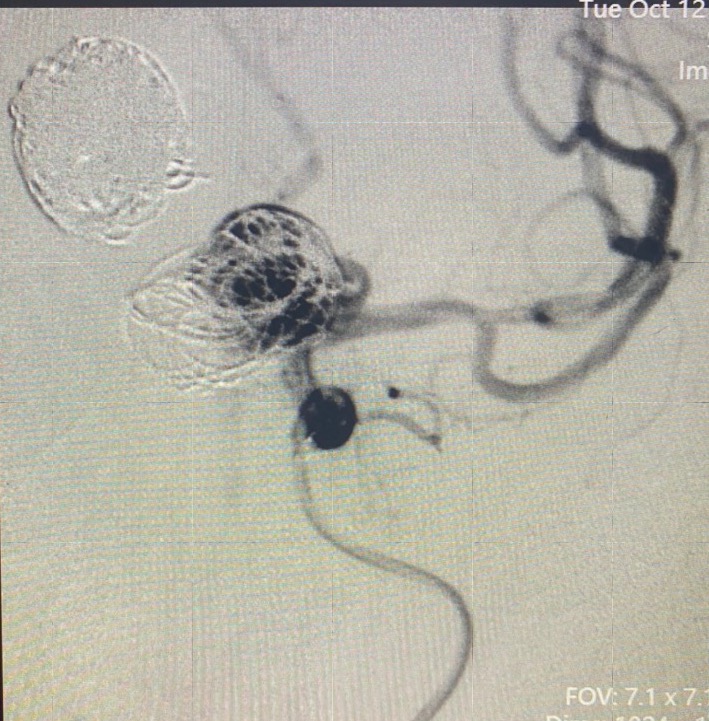

然后填圈至动脉瘤中、上部致密填塞,下部近分支处疏松填塞,同时释放左侧EP2支架,尾端紧贴pipeline侧方呈T形放置。最后稍推拉完全pipeline至基底动脉中下段。(这是本次手术有瑕疵的地方,尾端覆盖基底动脉稍长了一些,与我们测量计算误差有关)

术后即刻造影显示瘤体中上部已完全不显影,仅下部可见造影剂,基底动脉各分支显影良好。

术中先行后循环造影显示:动脉瘤几乎完全不显影,各分支显影良好。这个效果还是有些出乎我们的意料的好,大概率消除了迟发性出血这个隐患。